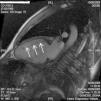

Miocardiopatia no compactada presentándose como ictus de repetición

Non-compacted cardiomyopathy, presenting as repeated stroke